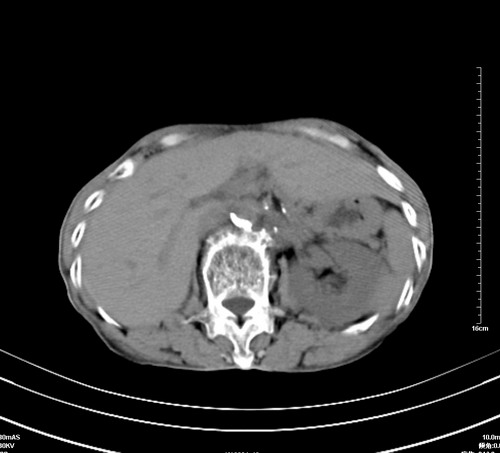

病人,女,79岁,主要因腹疼二月入院,彩超,肝,胆,脾,未见异常,胸透上消化道造影未见异常,化验白细胞增高,内科医生让做胸部ct检查,因为熟人多做了腹部(外科会诊考虑胆囊炎).现ct片如下请假各位战友.

1 气管旁、隆突下淋巴结明显肿大,肝左叶外侧段低密影,都考虑转移。

2 肝右后叶下段明显增大,片状低密影,但因各种伪影显示不佳,不排除病变。

后中纵隔团块影,伴气管、食道受压移位,首先考虑转移瘤,肝s5段低密度灶。建议增强检查,另外其结肠是否有问题请提供,右肺部分肺叶局限含气增多,考虑局限肺气肿。

后中纵隔团块影,伴气管、食道受压移位,首先考虑转移瘤,肝表现同11773。